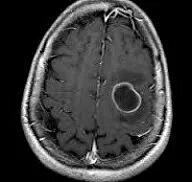

Абсцесс головного мозга

На поздних стадиях энцефалита очаг приобретает округлые и ровные контуры. Контрастное вещество равномерно распределяется по периферии очага, не меняя плотности его центральной зоны. Однако при повторной КТ через 30-40 минут наблюдается диффузия контраста в центр капсулы, а также его присутствие в периферической зоне, что не свойственно злокачественным опухолям. Абсцесс мозга, заключенный в капсулу, выглядит на КТ как округлое объемное образование с четкими и ровными контурами повышенной плотности (фиброзная капсула). В центре капсулы наблюдается зона сниженной плотности (гной), а по периферии видна зона отека. Введенное контрастное вещество скапливается в виде кольца вдоль контура фиброзной капсулы, с небольшой примыкающей зоной глиоза.

Магнитно-резонансная томография головного мозга является более точным методом диагностики. На ранних стадиях формирования мозгового абсцесса (1-9 суток) энцефалитический очаг выглядит следующим образом: на Т1-взвешенных изображениях - снижение сигнала, на Т2-взвешенных изображениях - повышение сигнала. На поздних стадиях (капсулированный абсцесс) на Т1-взвешенных изображениях абсцесс представляет собой зону сниженного сигнала в центре и на периферии (в зоне отека), а контур капсулы имеет повышенный сигнал. На Т2-взвешенных изображениях центр абсцесса может быть изо- или гипоинтенсивным, а периферическая зона (зона отека) - гиперинтенсивной. Контур капсулы четко виден.